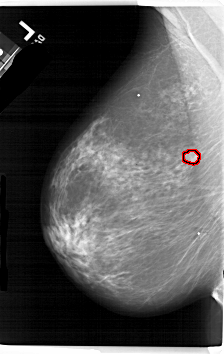

A_1657_1.LEFT_MLO

FILE: A_1657_1.LEFT_MLO.OVERLAY

TOTAL_ABNORMALITIES 1

ABNORMALITY 1

LESION_TYPE MASS SHAPE LOBULATED MARGINS OBSCURED

ASSESSMENT 4

SUBTLETY 3

PATHOLOGY MALIGNANT

TOTAL_OUTLINES 1

BOUNDARY